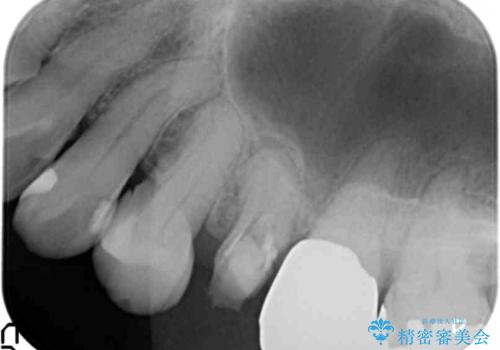

- 左上5番の根の治療途中で転院希望で来院。

割れているために抜かないといけないと説明されたとのことでした。

特に割れている所見はなかったため、根の治療から被せ物まで治療を行いました。